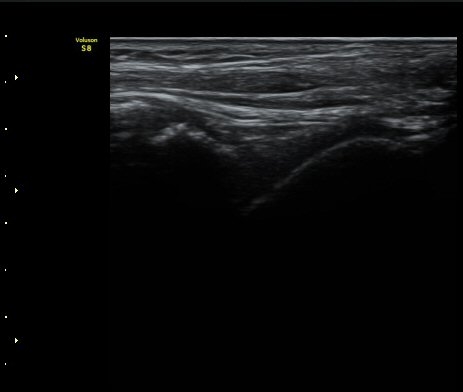

ÃÊÀ½ÆÄÅõ½ÃÇÏ ºÎÇϰ˻翡¼­ ºñ°ñ°ú °ß¿­°ñÀý °ñÆí»çÀÌ¿Í ºñ°ñ°ú °Å°ñ »çÀ̰¡ ¹ú¾îÁø´Ù

(樨毢 1)